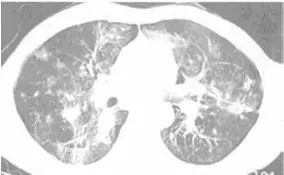

下面是另外1例,临床诊断,单独氟康唑治疗好转,CT示多发空洞,肺念珠菌病空洞少见,算是一例不太典型的CT。[2]

图2